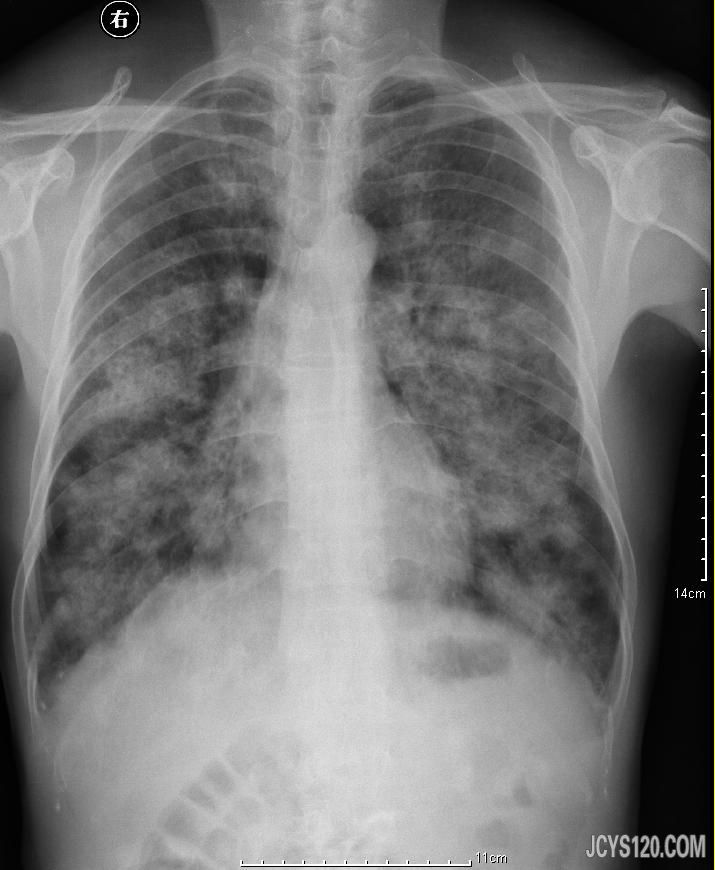

男67岁,咳嗽咳黄痰,否认近期咯血、高烧,否认慢支、结核等病史,查体不热,煤矿工人数十年未曾体检。 阅读全文>